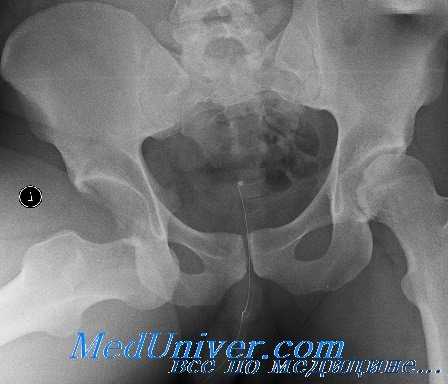

Для уточнения диагноза выполняют обзорную рентгенографию таза и рентгенографию поврежденного сустава в трех дополнительных проекциях. По возможности пациента направляют на КТ таза, поскольку эта методика позволяет более точно оценить тяжесть травмы и характер смещения отломков. Диагностическая ценность компьютерной томографии возрастает при повреждениях задней колонны и оскольчатых переломах.

Переломы вертлужной впадины могут оказаться трудными для выявления на первичных рентгенограммах таза в прямой проекции. При подозрении на эти повреждения важно тщательно изучить нормальные анатомические ориентиры, окружающие вертлужную впадину и изображенные на рис. 176. При подозрении на перелом вертлужной впадины следует сделать рентгеновские снимки в следующих проекциях:

1) переднезадняя проекция таза;

2) переднезадняя проекция бедра и тазобедренного сустава на стороне повреждения;

3) наружная косая проекция под углом 45°;

4) внутренняя косая проекция под углом 45°.

Задняя опора и передняя губа лучше просматриваются на снимке в наружной косой проекции под углом 45°, в то время как задняя губа и передняя опора — на снимке во внутренней косой проекции под углом 45°. Кроме того, переломы заднего столба будут искажать подвздошно-седалищную линию, в то время как переломы передней опоры приведут к деформации подвздошно-лонной линии. Центральные переломы вертлужной впадины лучше выявляются на задней косой проекции. Некоторые виды переломов таза нередко сочетаются с переломами вертлужной впадины, которые не всегда легко выявить рентгенологически.

Прямая проекция тазобедренного сустава (вертлужной впадины). У больного с подозрением на перелом следует тщательно осмотреть эти линии. При скрытом переломе может наблюдаться смещение только одной из этих линий